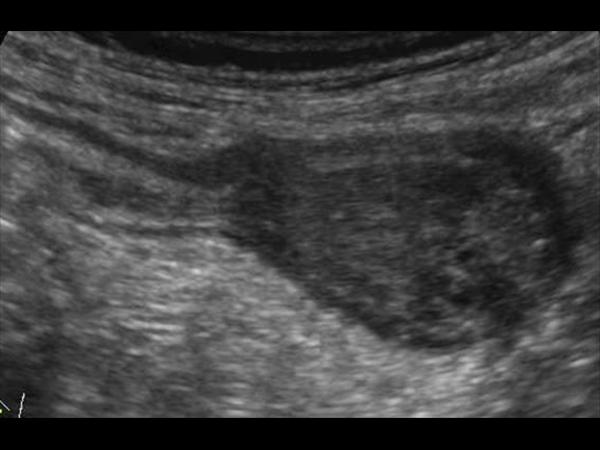

Mucocele ruột thừa

» Thông tin: Nam giới – 71 tuổi.

» Lâm sàng: Đau hố chậu phải mạn tính.